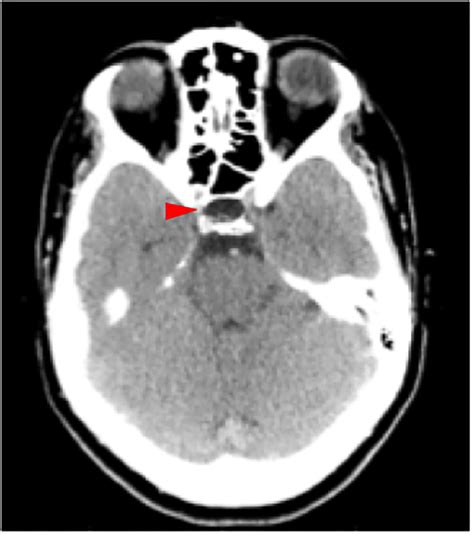

Diagnosing a Partial Empty Sella involves a combination of clinical evaluation, imaging studies, and hormonal tests. The diagnostic process typically includes:

• Imaging Studies: Magnetic Resonance Imaging (MRI) is the gold standard for visualizing the pituitary gland and the sella turcica. It can show the extent of the empty sella and any associated abnormalities.

• empty sella syndrome radiology

• partial empty sella ct